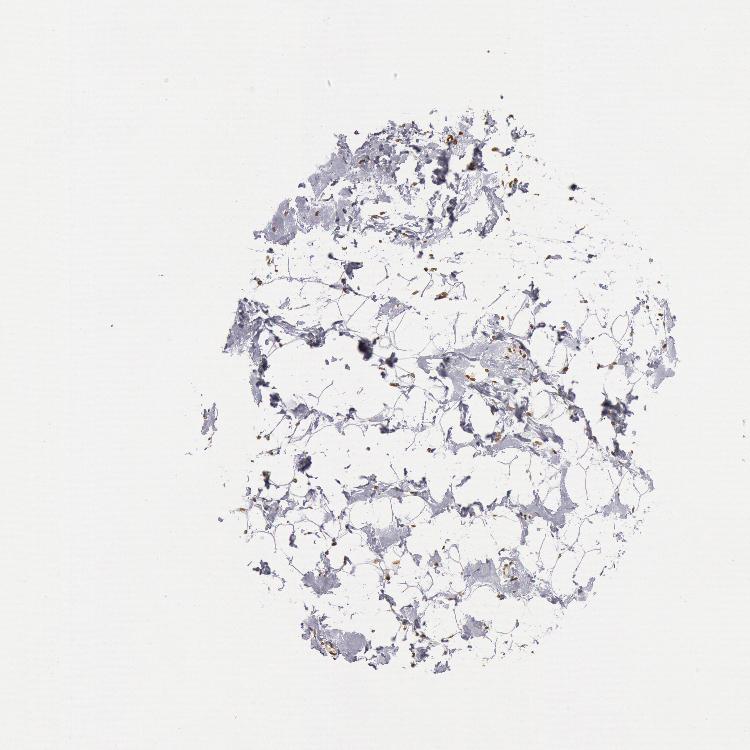

BREAST - Antibody stainingi

Antibody staining in the annotated cell types in the current human tissue is reported as not detected, low, medium, or high, based on conventional immunohistochemistry profiling in selected tissues. This score is based on the combination of the staining intensity and fraction of stained cells.

Each image is clickable and will lead to virtual microscopy that enables deeper exploration of all samples and also displays staining intensity scores, fraction scores and subcellular localization as well as patient and tissue information for each sample.

Antibody HPA001209

Adipocytes Medium

Glandular cells High

Myoepithelial cells High